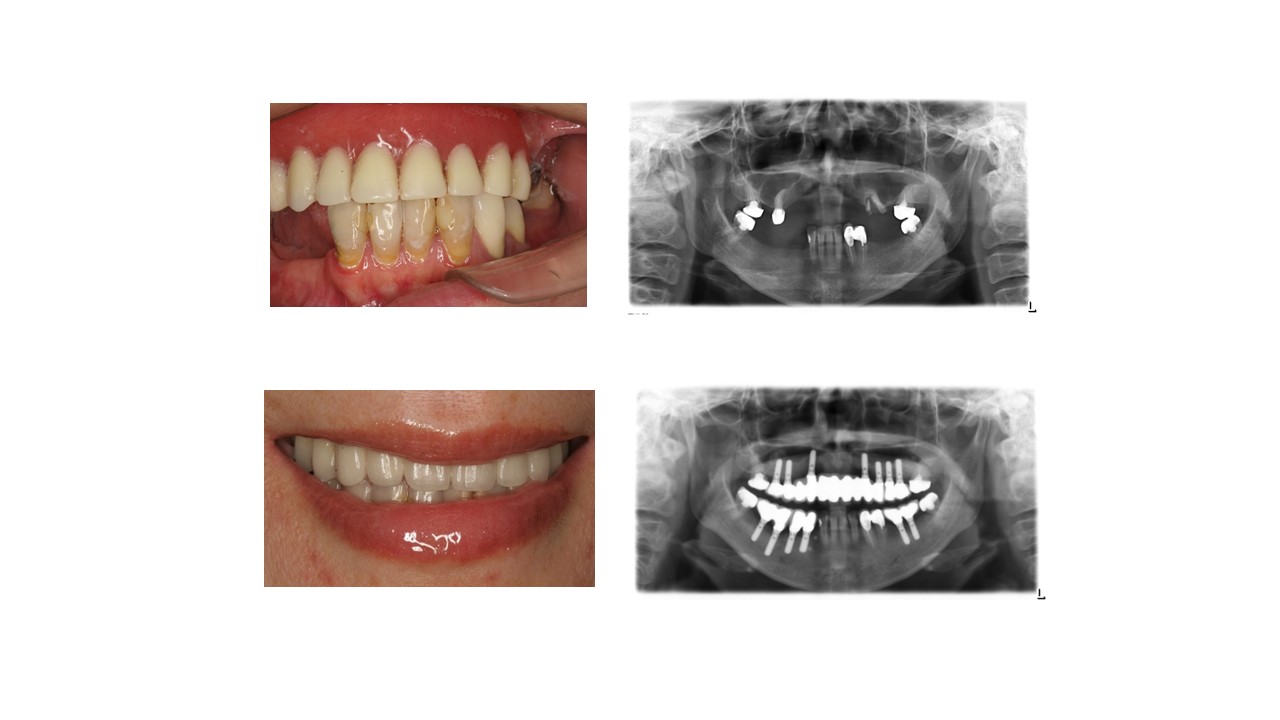

种植科普